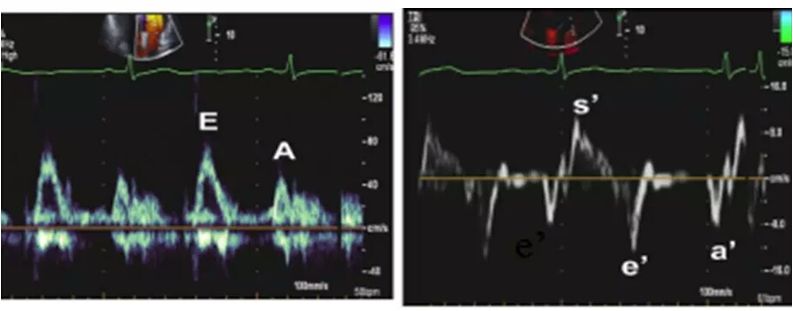

★ E/e´ ≧13,平均室间隔及侧壁e´ 均<9cm/s